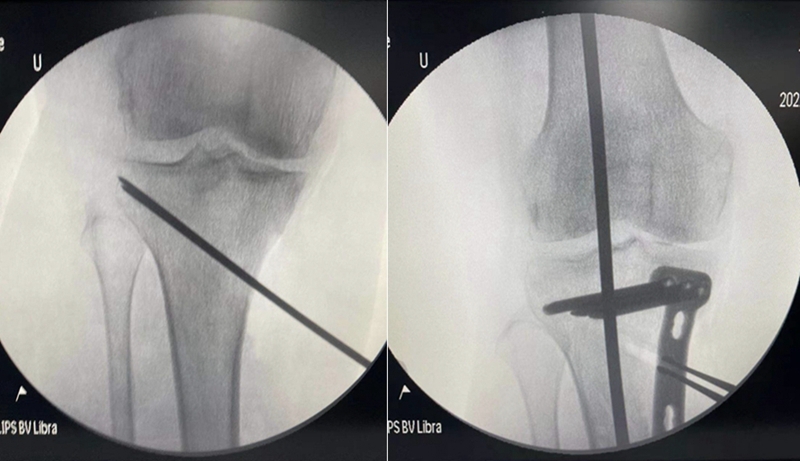

术中关节镜证实外侧软骨良好,取出游离体,内侧清理后行胫骨高位截骨术。

术后影像